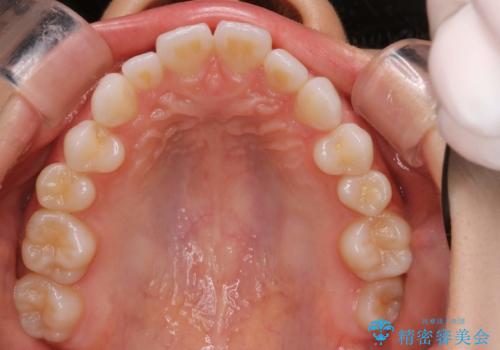

インビザラインで出っ歯を改善する 抜歯をしないinvisalign治療

- 非抜歯・遠心移動による前突の改善をマウスピースにて計画した。

非抜歯矯正の場合、大きく前歯を下げることはできませんが、奥歯の遠心移動や歯のサイズダウンにより歯軸を立て、見かけ上の出っ歯感をある程度改善することができます。